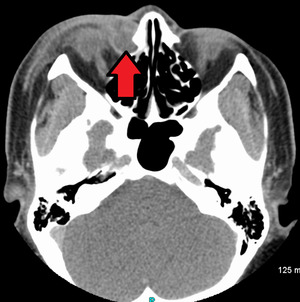

A case of dacryocystitis as seen on CT scan